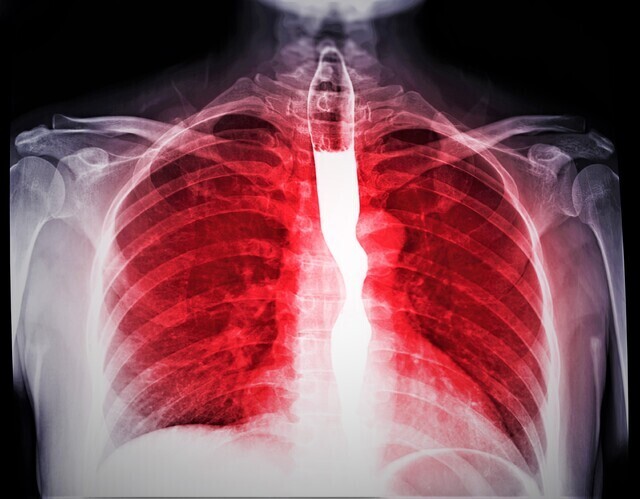

속쓰림이 반복된다면 이미 식도가 손상되고 있을 수 있다. 게티이미지 전문가들은 “이 작은 신호가 장기적 손상의 시작일 수 있다”고 경고한다.